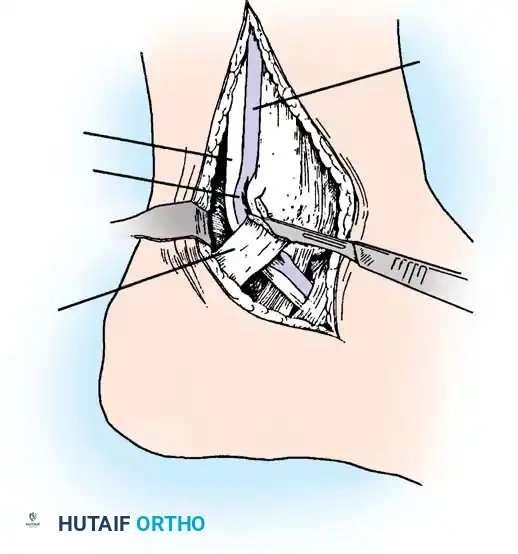

2. Surgical Approach

Begin the incision 10 to 12 cm proximal to the tip of the lateral malleolus, positioned approximately 1 cm posterior to the subcutaneous border of the fibula. Continue the incision distally and slightly obliquely to accommodate the bulbous posterior aspect of the lateral malleolus. Curve the incision gently 1 cm distal to the tip of the lateral malleolus, extending toward the base of the fifth metatarsal for another 3 to 4 cm.

Surgical Pitfall: The sural nerve and the small saphenous vein course just posterior to the peroneal tendons and are strictly subcutaneous at this level. Meticulous dissection is required to avoid iatrogenic neuroma formation, which can be more debilitating than the primary tendon pathology.

3. Retinaculum Release and Exploration

Open the sheath of the peroneal tendons proximally and trace the tendons distally to the superior peroneal retinaculum (SPR).

- If the tendons appear normal both proximal and distal to the SPR, incise only half of the retinaculum (about 1 cm or less) to preserve its stabilizing function.

- If the SPR is thickened or the sheath is fibrotic—suggesting impaired tendon excursion—incise the entire retinaculum and inspect the inferior peroneal retinaculum (IPR). In isolated tenosynovitis, it is unusual to require the release of both retinacula.

Carefully evaluate the septum that extends from the fibula to the SPR, separating the peroneus longus and brevis. An accessory peroneal tendon (peroneus quartus) may be present in a separate compartment, contributing to overcrowding and stenosis. Release this septum and inspect the peroneus brevis, looking for any accessory slips.

4. Tenosynovectomy and Tendon Debridement

Perform a complete tenosynovectomy, sharply debriding hypertrophic portions of the tendon sheath with a small rongeur or dissecting scissors. The findings at surgery represent a continuum: from clear fluid and relatively normal-appearing tendons, to small linear tears, to thickened, fibrotic sheaths encasing grayish, degenerative tendons.

Inspect the tendons meticulously for attritional, longitudinal fissuring. This pathology is most commonly located on the deep (anterior) surface of the peroneus brevis tendon, where it is compressed against the fibula by the overlying peroneus longus.